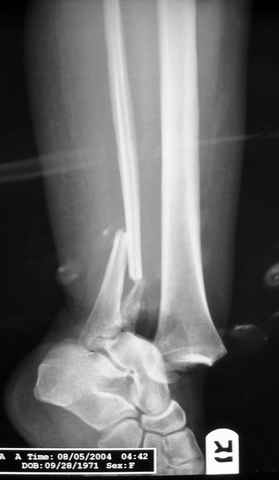

Dear all,40 y.o. man had sustained this terrible fracture falling from a motorbike.

Closed fracture.

This is really Pilon Fx (C3.3; the high energy and the extent of distal tibia comminution are defining it).